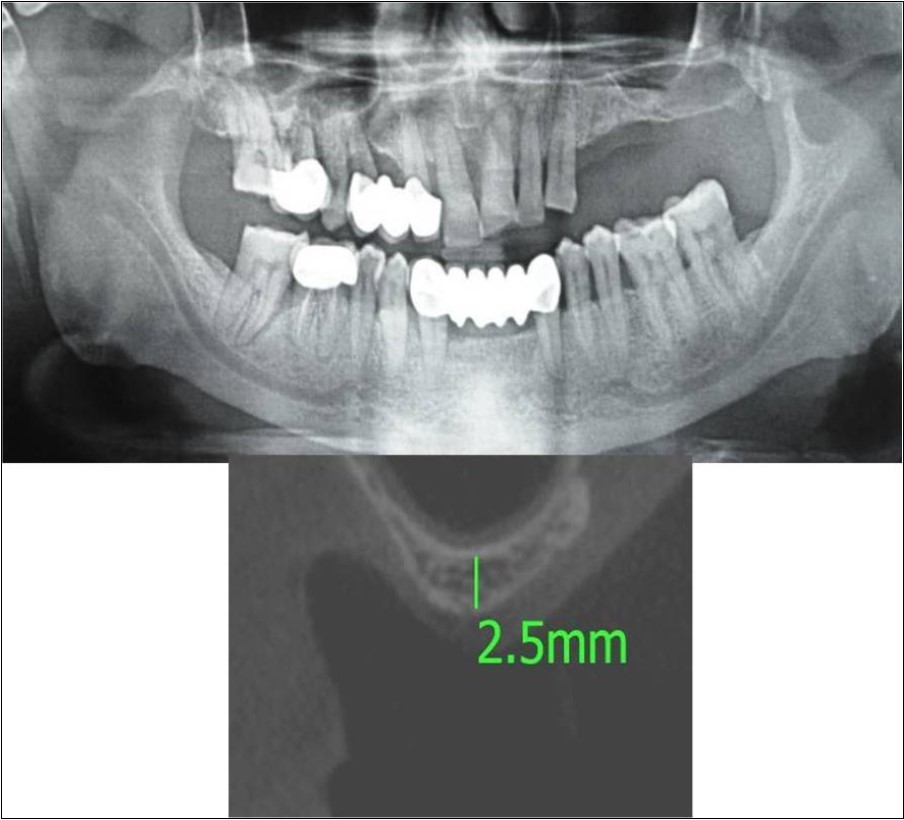

Clinical and Radiological Assessment:

3.Height of available bone- 2.5mm;

Treatment:

Patient underwent the procedure of direct sinus elevation using sinus lateral approach kit. After crestal and vertical release incisions, muco-periosteal flap was raised to expose the buttress region. A bony window of 1cm diameter was created; sinus lining identified and elevated up to receive calcium phosphosilicate as graft material and closure was achieved under local anaesthesia and strict aseptic protocols. Implant placement was planned to be carried-out after a period of 6 months to allow for the consolidation for graft and naive bone formation. At the end of 6 months, a repeat CBCT scan was advised to evaluate the increase in bone height. (Figure 15a,b, pre-treatment; Figure 16a,b, post-treatment)

Figure 15.a,b. Pre-treatment OPG and cross section of CBCT showing residual alveolar bone height for Case No.5;